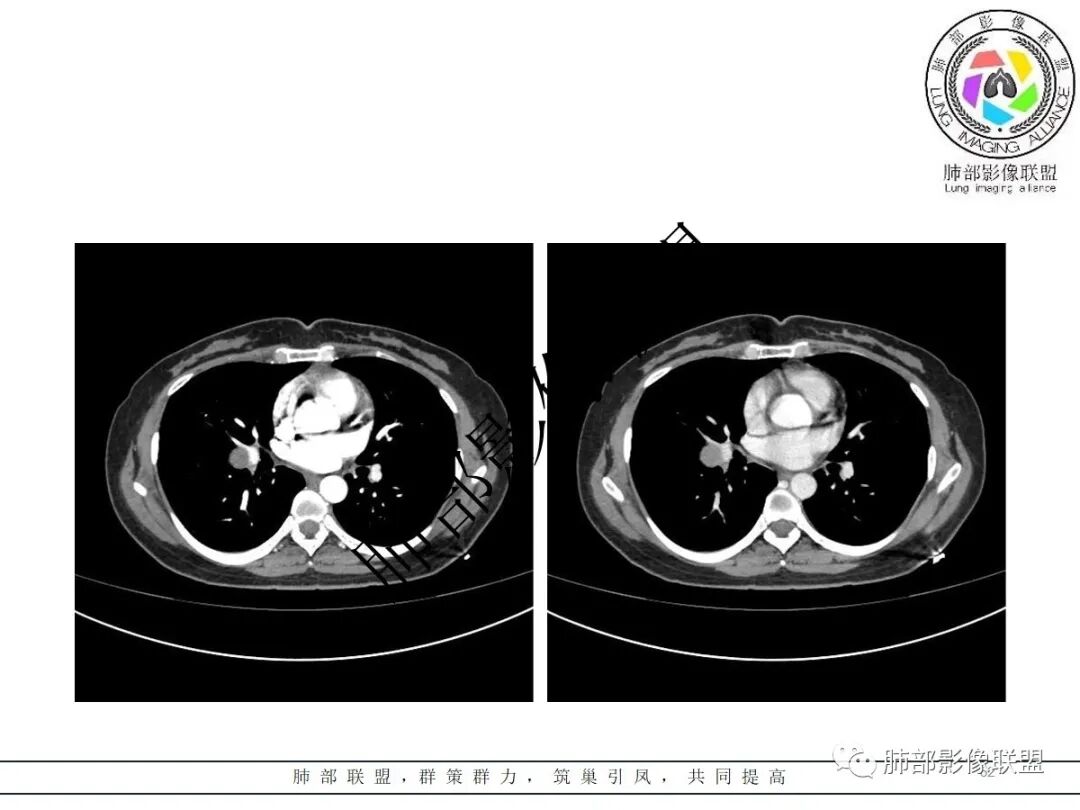

右肺门类圆形实性肿块,边缘光滑,无分叶毛刺,跨叶,推移血管,密度均匀,增强延迟强化相对明显,未见坏死及血管造影征。

3.病灶密度均匀,未见液化坏死、钙化及脂肪低密度。轻度强化,可见纤细血管影蜿蜒穿行。右肺动脉推移变形,未见侵入或充盈缺损。

3)硬化性肺细胞瘤(PSP)可以血管贴边,常常强化比较显著。

4)发生于肺表面(近脏层胸膜或叶间裂),强化不显著,可见穿行血管,与本例的符合程度是最高的。

3)CT増强多呈中度至明显均匀强化,多期扫描呈持续性强化,部分病灶早期强化不均匀,呈花斑状,延迟后强化较早期均匀;

4)瘤周可出现晕征、空气新月征及贴边血管征,若同时出现,诊断PSP的信心更好。